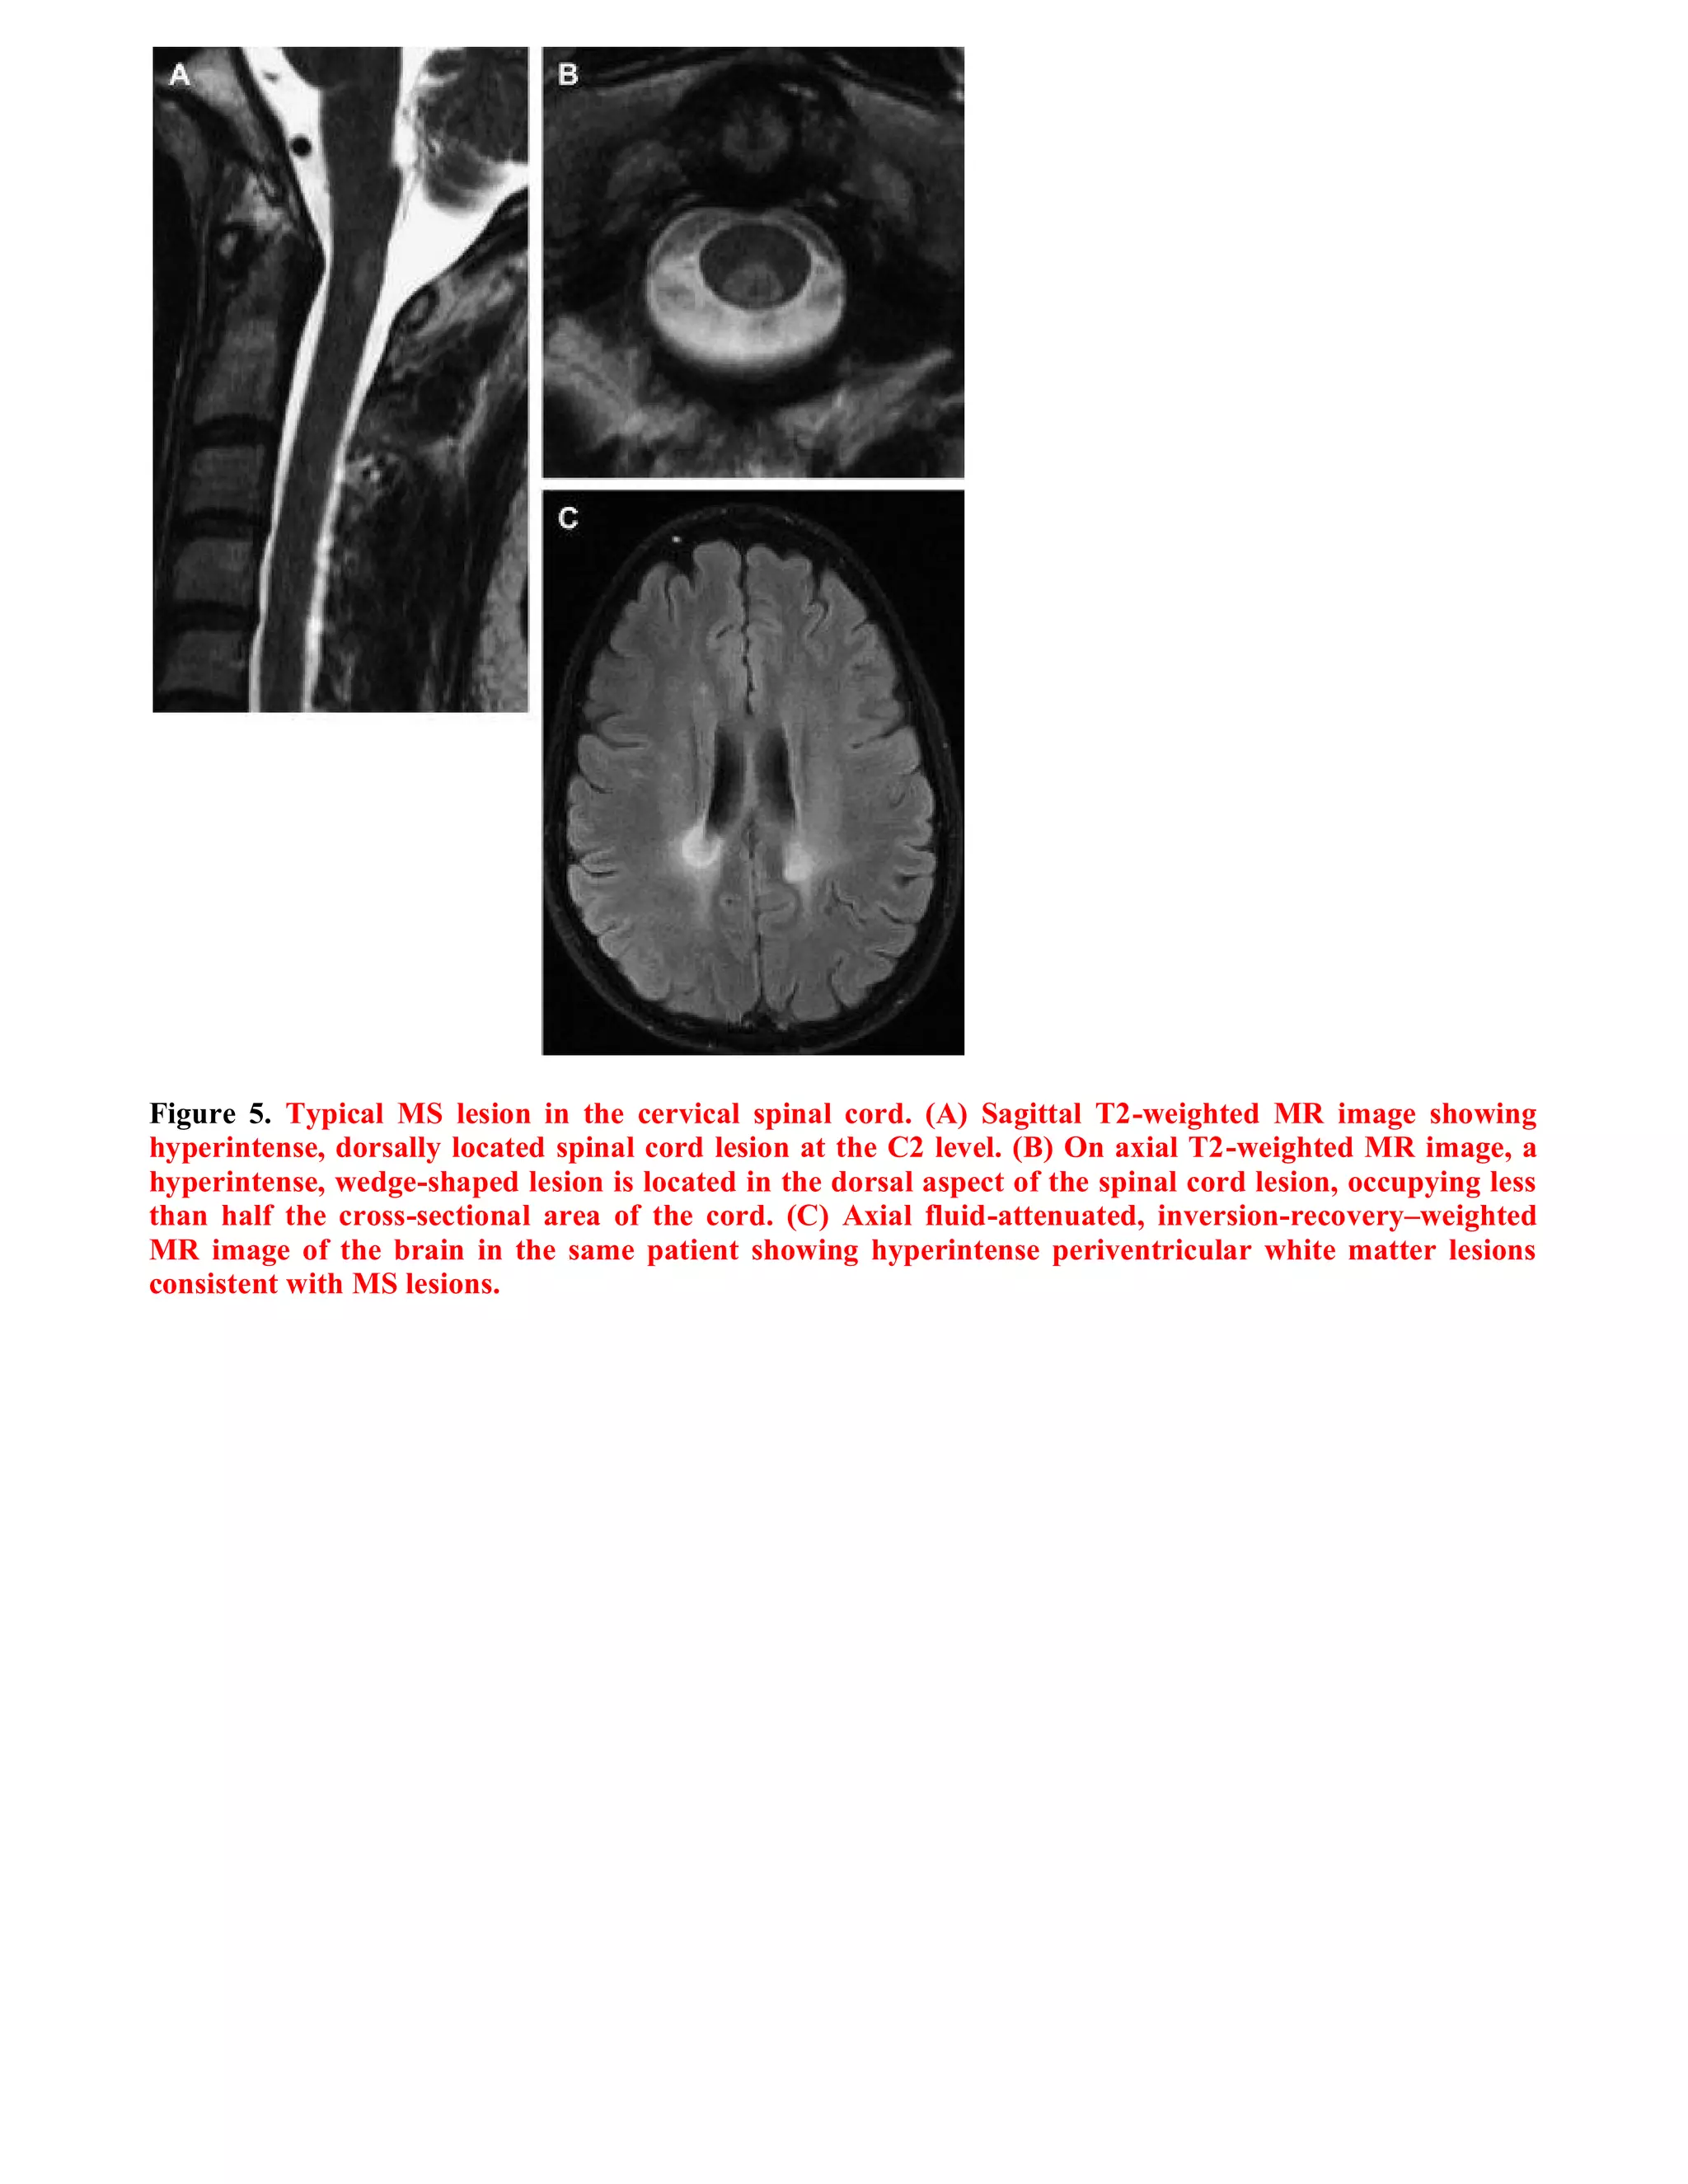

This document summarizes a case study of spinal multiple sclerosis seen on MRI imaging. It includes the following key points: 1) MRI images of the patient show multiple well-defined pencil-shaped lesions occupying 2-3 spinal segments that appear hypointense on T1-weighted images and hyperintense on T2-weighted images. 2) The lesions are characteristic of multiple sclerosis and located peripherally within the spinal cord. 3) The imaging and clinical presentation lead to a diagnosis of spinal multiple sclerosis.